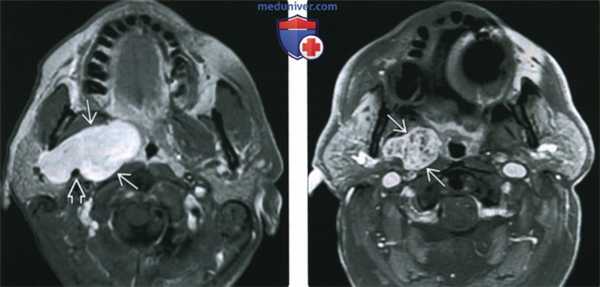

(Слева) На аксиальной МРТ (Т1ВИ С+ FS) в глубокой доле околоушной железы определяется большая опухоль с бугристыми краями, равномерно накапливающая контраст. Шиловидный отросток вдавливает задний край новообразования, что свидетельствует о нахождении опухоли (ДСО) в околоушном пространстве.

(Справа) На аксиальной МРТ (Т1ВИ С+ FS) в глубокой доле околоушной железы определяется опухоль неравномерно накапливающая контраст. Контрастирование ДСО варьирует: может быть равномерным, неравномерным, минимальным.